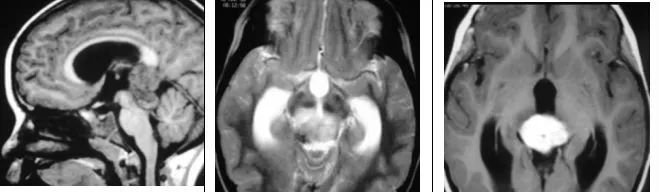

影像特征

12岁儿童,矢状位T1WI示松果体区低信号肿块,横断位T2WI示一高信号肿块右份伴局灶性低信号,代表钙化,注意与病灶相关的脑积水;横断位及矢状位T1WI+C示明显强化肿块